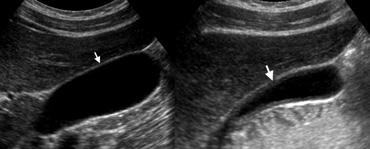

TRÁI: Siêu âm túi mật bình thường sau nhịn ăn qua đêm cho thấy thành túi mật là một đường tăng âm mỏng như bút chì (mũi tên). PHẢI: Siêu âm ở trạng thái sau ăn cho thấy hình ảnh dày thành túi mật giả.

Thành túi mật bình thường trên siêu âm có hình ảnh là một đường tăng âm mỏng như bút chì.

Độ dày thành túi mật phụ thuộc vào mức độ căng giãn của túi mật và hiện tượng dày thành giả có thể xảy ra ở trạng thái sau ăn.

TRÁI: Siêu âm ở phụ nữ 59 tuổi bị viêm túi mật cấp cho thấy hình ảnh phân lớp của thành túi mật dày, với vùng giảm âm giữa các đường tăng âm. PHẢI: Trên CT có thuốc cản quang, túi mật thành dày chứa lớp ngoài giảm tỷ trọng (mũi tên) do phù nề dưới thanh mạc.

Thành túi mật được coi là dày khi đo hơn 3 mm, thường có hình ảnh phân lớp trên siêu âm [1], và trên CT thường chứa một lớp giảm tỷ trọng của phù nề dưới thanh mạc có thể nhầm lẫn với dịch quanh túi mật [2].